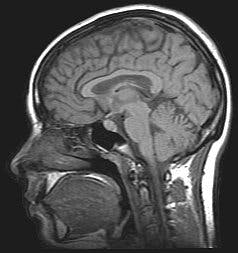

De communicatiebarrière van ons brein11 oktober 2013De communicatiebarrière van ons breinHet moet vreselijk zijn om verlamd te raken, maar de laatste jaren worden er voorzichtige successen geboekt met direct door de hersenen te besturen protheses. Toch leggen deze dure en vaak logge ma...

Diepe hersenstimulatie verstoort communicatie in het brein27 april 2013Diepe hersenstimulatie verstoort communicatie in het breinDiepe hersenstimulatie werkt anders in op onze hersenen dan altijd werd gedacht. Neurowetenschappers toonden dit aan bij de behandeling van patiënten met een obsessief compulsieve stoornis.